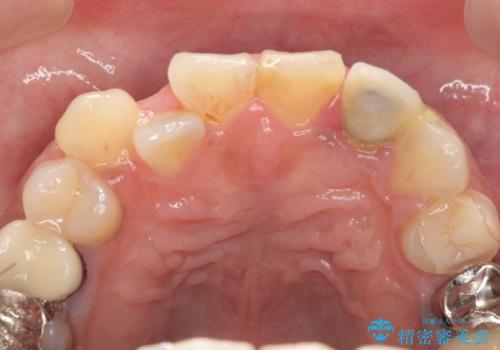

- 左上2番目の歯がグラグラするので診て欲しいといらっしゃった方の症例です。

左上2番目の歯は歯根が破折してため抜歯し、左上123のブリッジによる欠損補綴を行いました。

左上4、5番目の歯は根尖病変を認めたため再根管治療を行い、オールセラミッククラウンによる補綴を行いました。

なお左上4に関しては縁下歯質を改善するため、歯冠挺出を行っております。